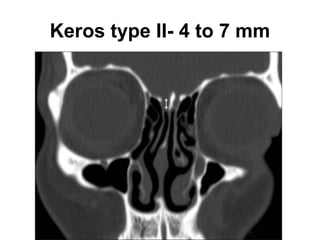

Olfactory fossa

• The depth of the olfactory fossa is determined by

the height of the lateral lamella of the cribriform

plate, which is part of the ethmoid bone. In 1962,

Keros had classified the depth of the olfactory

fossa into three types, that is,

• Keros type I: <3 mm,

• type II: 4-7 mm , and

• type III: 8-16 mm.-Kero type III is most

vulnerable to iatrogenic injury.

Keros type II- 4 to 7 mm